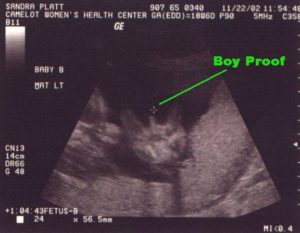

Врач оценивает угол, сформированный между спинкой ребеночка и половыми органами. Угол меньше 30 градусов указывает на развитие девочки. Предположения о появлении на свет мальчика могут возникнуть, если этот угол больше 30 градусов.

При оценивании развития костной системы ребенка, обращают внимание на конфигурацию черепа. Мальчики, чаще всего имеют ярко выраженную челюсть, квадратные очертания головы. У девочек головка более округлая.

Существует специальная техника определения половой принадлежности плода, которую описали врачи еще в 1999 году. Она заключается в интерпретации угла наклона, образовавшегося уже полового бугорка.

Данный метод может использоваться врачами начиная с 12-й недели. Достоверность расчетов равна 85-90%, а с 13-й недели – 95%.

Учитывая многолетний опыт врачей, таким методом беременным предоставляются верные расчеты половой принадлежности их ребенка с точностью до 95%. Ошибиться врач может при неправильной интерпретации угла наклона. В случае если существует риск ошибки, врач предпочитает не сообщать сомнительную информацию будущей матери.